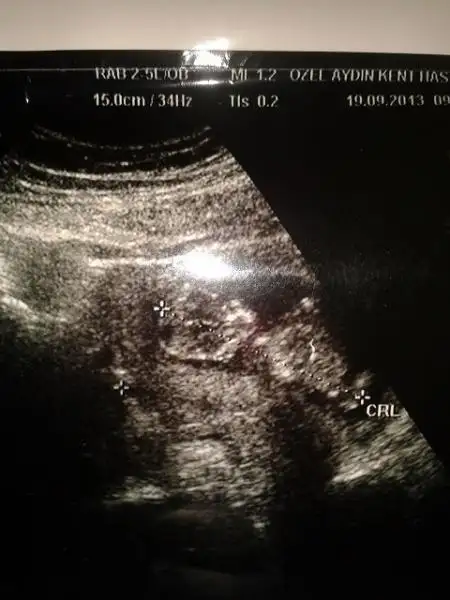

rica etsem benim bebeğimede bakabilirmisiniz lütfennn :)Eki Görüntüle 811667 Eki Görüntüle 811668

tam yükleyemedim galiba anlayamazsanız tekrar yüklerim

Bana kiz gibi geldi.nub belirgin sekilde paralel diyorum ben.